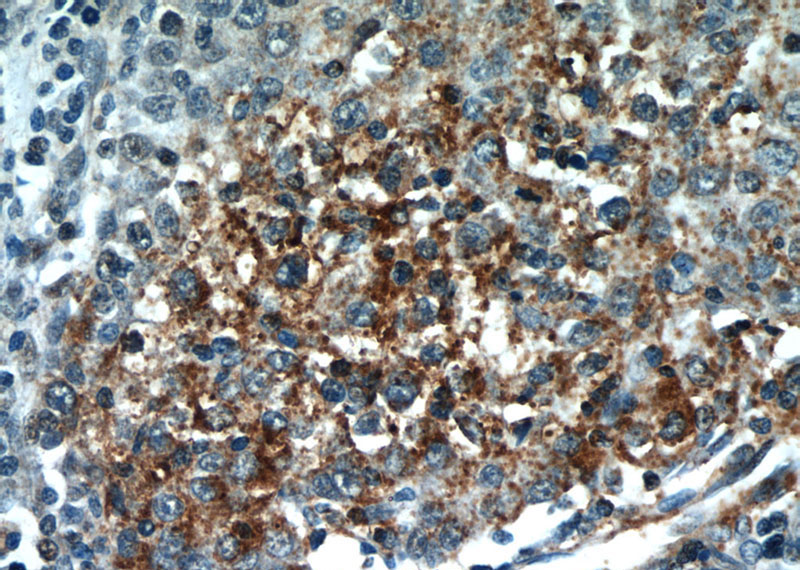

Immunohistochemical of paraffin-embedded human liver cancer using Catalog No:113872(PIK3CB antibody) at dilution of 1:50 (under 40x lens)